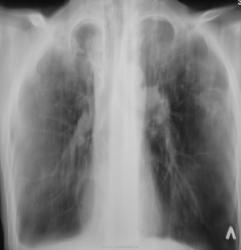

Валентин Львович, полости на верхушках обозвали кавернами?..

Вы правы, в ОПТД, именно так и обозвали. Хотя, у нас было сомнение, что это "каверкоты", учитывая внутренний контур.